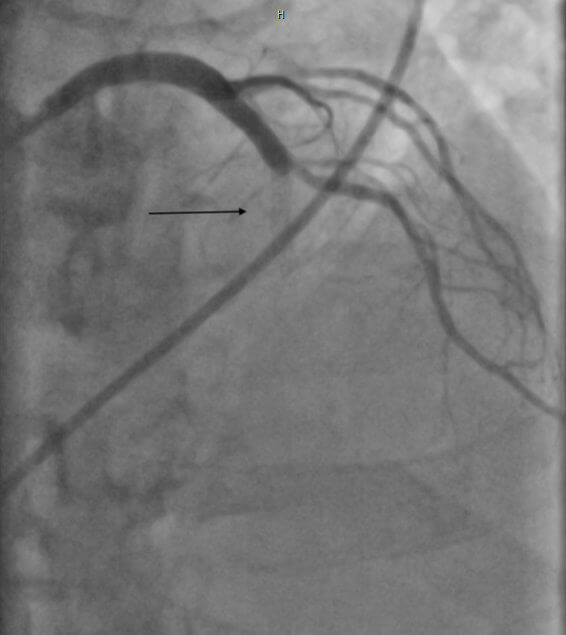

Definitionsgemäß liegt eine ISR dann vor, wenn eine Verengung > 50 % innerhalb des Stents, aber auch jeweils 5 mm nach distal oder proximal außerhalb des gestenteten Abschnitts liegt.

Die Behandlung der ISR ist immer eine Herausforderung und wird aufgrund der unterschiedlichen Datenlage kontrovers diskutiert. Grundsätzlich erscheint es wichtig, im Vorfeld die Ursache eines Stentversagens (z. B. Unterexpansion, Fraktur oder Malapposition) näher zu evaluieren, weshalb hier die intravaskuläre Bildgebung zum weiteren Informationsgewinn erwogen werden kann.

Gerade durch die OCT-Untersuchung lässt sich zudem das Vorhandensein einer Neoatherosklerose beurteilen. Je nachdem welcher Mechanismus als Ursache für das Auftreten einer ISR in der intravaskulären Bildgebung identifiziert wird, kann eine spezifische Therapie eingeleitet werden, unter der Verwendung von speziellen modernen Devices.